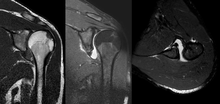

MRI of shoulder after dislocation with Hill-Sachs lesion and labral Bankart's lesion.

A systematic review of published literature concerning dislocation of the shoulder has indicated that young adults engaged in highly demanding sports or job activities should be considered for operative intervention to achieve optimal outcome.[24] Arthroscopic surgery techniques may be used to repair the glenoidal labrum, capsular ligaments, biceps long head anchor or SLAP lesion and/or to tighten the shoulder capsule.[25]

Arthroscopic stabilization surgery has evolved from the Bankart repair, a time-honored surgical treatment for recurrent anterior instability of the shoulder.[26] However, the failure rate following Bankart repair has been shown to increase markedly in patients with significant bone loss from the glenoid (socket).[27] In such cases, improved results have been reported with some form of bone augmentation of the glenoid such as the Latarjet operation.[28][29]